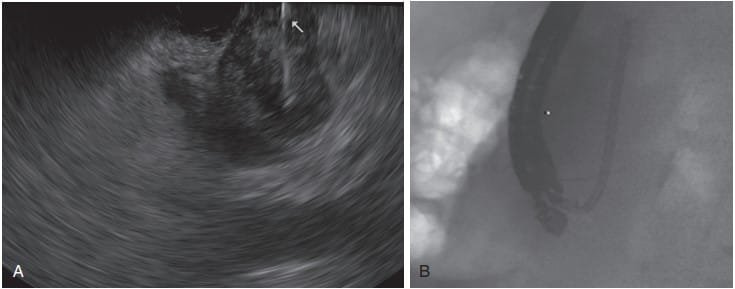

EUS-Guided Fine-Needle Aspiration: The Gold Standard for Tissue Acquisition

EUS-guided fine-needle aspiration (EUS FNA) is considered the gold standard for obtaining tissue samples from pancreatic mass lesions. The diagnostic yield of EUS FNA can be maximized through the use of the fanning technique and the presence of a cytopathologist for on-site diagnosis. In centers without on-site cytopathology support, recently available core biopsy needles enhance the diagnostic yield.